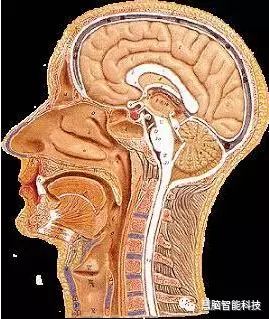

让我们使用半球横截面看看大脑的主要部分。这是你脑袋里大脑的样子:

现在,让我们把大脑取出来,并删除左半球,这让我们能看清楚内部。